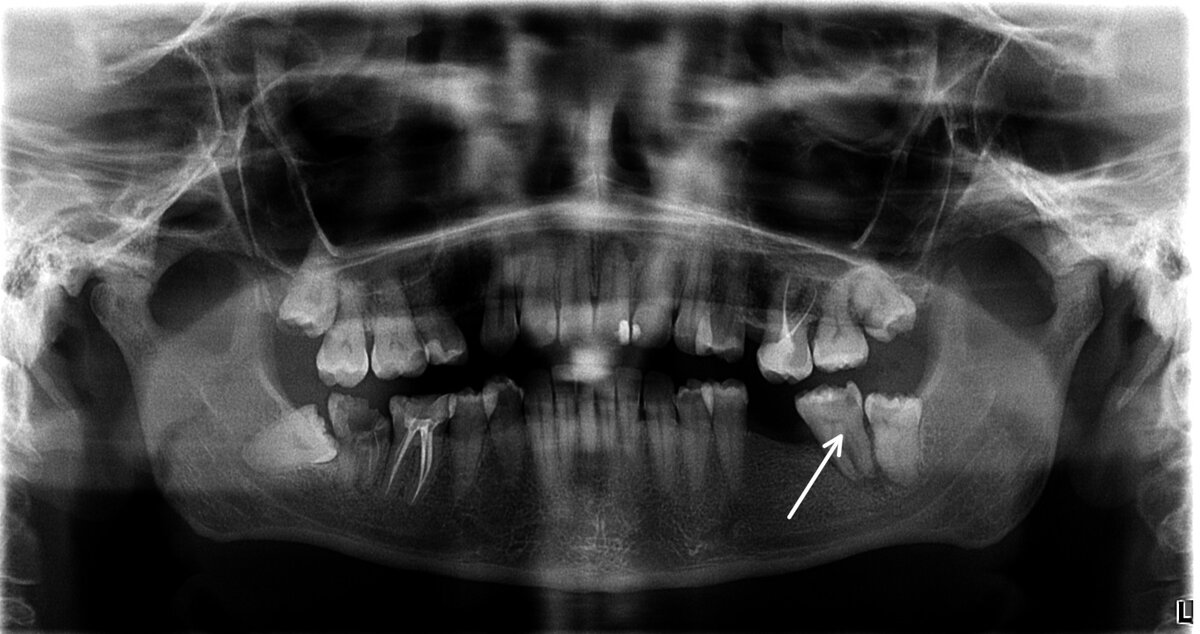

Ко мне пришла пациент молодого возраста на приём с жалобами на подвижность зуба 3.7 (слева снизу) и желанием установить имплантаты в области отсутствующих зубов.

Ортопантомограмма:

По левой стороне феномен Попова Годона (деформация зубных рядов). Отсутствие зубов 2.5,3.6, выдвижение вниз зуба 2.6, наклон зуба 3.7, кариозный процесс на зубе 3.5, оголение пришеечной области (опущение десны) и кариозный процесс между зубом 2.6 и 2.7. Вот такие дела получились из-за длительного отсутствия всего двух зубов по левой стороне.

В области отсутствующих 14 и 25 осталось мало места (из-за деформаций) для установки имплантатов и будущих коронок. В области 16 и 17 зуба вторичный кариес (тёмное место указано стрелочкой):

-12

В области резцов на нижней челюсти налёт, зубной камень. Место под имплантат в области 36 тоже недостаточно, так как 37 сдвинулся. Виднеется 38 зуб. 46 имеет дефект пломбы и в вторичный кариес. 47 разрушен и не подлежит восстановлению.

Исходя из полученных данных на осмотре и оптг снимка я предложил пациенту проконсультироваться с ортодонтом, для того чтобы все зубы вернуть на своё место, чтобы создать пространство под имплантаты и коронки на них. И проконсультироваться с ортопедом, чтобы составить альтернативный план лечения, без ортодонтии.